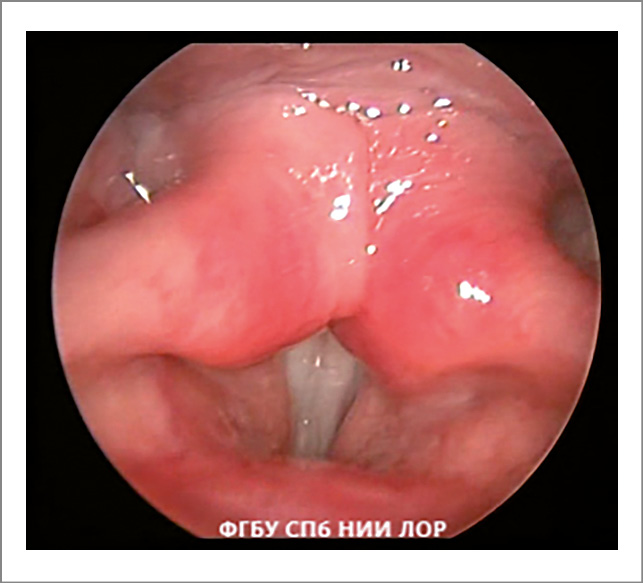

- Симптом «неоднородности» голосовых складок проявляется в том, что lig. vocale и m. vocalis видны изолированными друг от друга образованиями, а не как единое структурное целое (рис. 4).

Рис. 4. Функциональная дисфония по гипотонусному типу (фонация): симптом «неоднородности» голосовых складок.